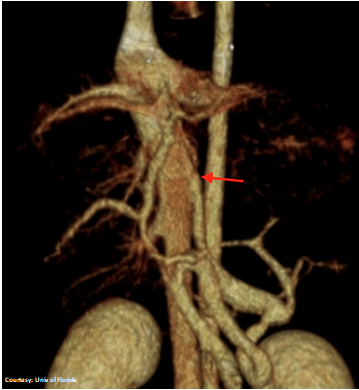

Does the RIGHT GASTRIC VEIN (RGV) contribute blood to the shunt?

WEISSE 2022